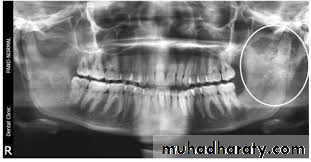

Raioraghical examination may demonstrate unlocular or multilocular types. Unilocular ameloblastomas may be confused with benign cysts. The tumors frequently absorbs the alveolus surrounding ,the roots of teeth and may absorb root ends.

Ameloblastoma grow by extension into adjacent tissues and may perforate the investing bone. A biopsy should precede treatment since

these tumors frequently present with individual characteristics.

Methods of treatment:

include extirpation, radical resection of the jaw. selective block excision and electro cauterization. Local excision of usually accessible tumor is indicated in the young.Provided, that they agree to regular follow - up and a radical resection when recurrence occurs. Recurrences are not unusual after curettage incomplete surgical treatment may stimulate tumor cell growth.